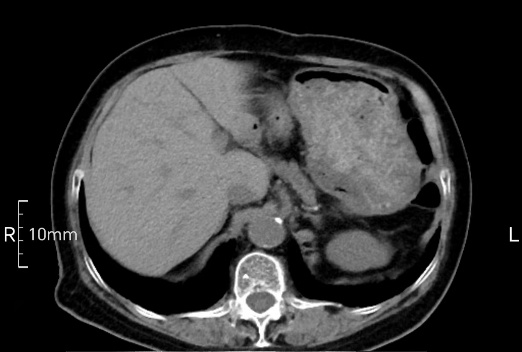

看看下面三幅便知遵醫(yī)囑的重要性。

完美禁食且喝飽飽,胃壁完美展現(xiàn)。